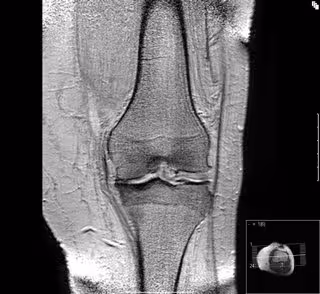

Artrosis de rodilla

Foto: UAM